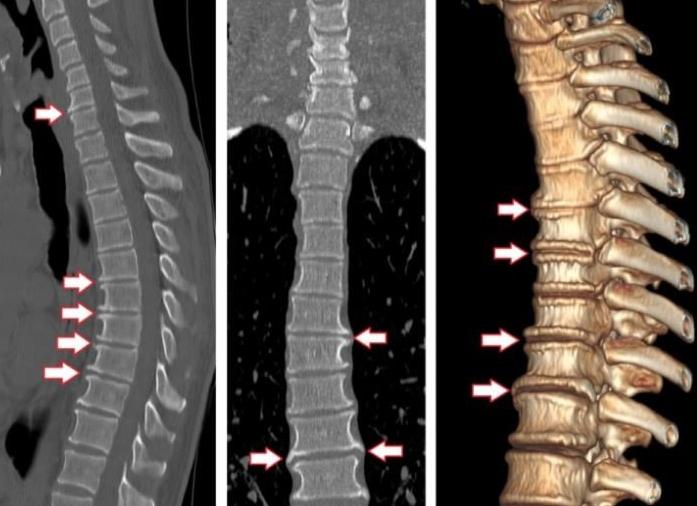

Магнитно-резонансная и компьютерная томография — высокотехнологические исследования, благодаря которым можно выяснить причину болей в пояснице, отеков, обнаружить болезнь почек, когда она еще никак не проявляется. Пациентам важно понимать, что лучше — КТ или МРТ почек, и на чем основывается врач, когда назначает тот или иной метод исследования.